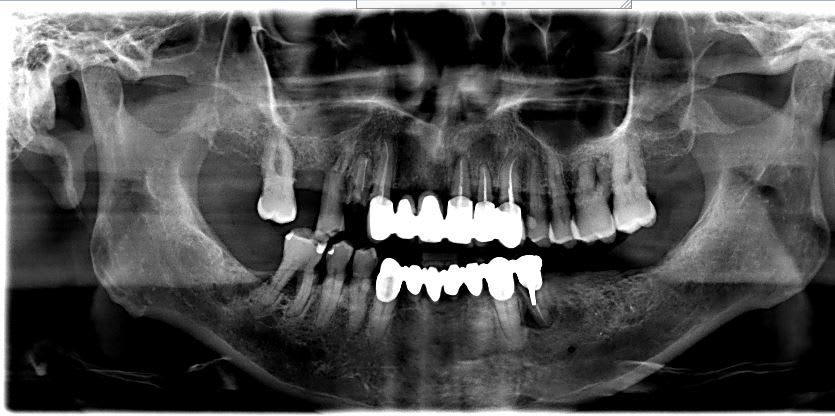

Bonjour j'ai un patient de 70 ans qui vient d'être traité pour un cancer orl, hygiène bucco dentaire pas terrible mais il a arrêté le tabac.

J'hésite un peu pour le plan de traitement pour le maxillaire.

En bas je pense extraire 46 et 34 et stelite ou implant

En haut il faut extraire 14 15 21 22. Les plans de traitement seraient:

- cr sur 13 et 23 + implants 12 22 et 14 16, mais pour le moment il n'a pas un super état général.

- cr sur 13 et 23 + stelite mais les crochets risquent de vite venir à bout de 13 et 23...

- grand bridge de 17 à 23 sur trois dents... ça me semble un peu holé holé... y en a t'ils parmis vous qui font ce type de bridge et je peux espérer faire tenir ça combien de temps...

voici la pano!